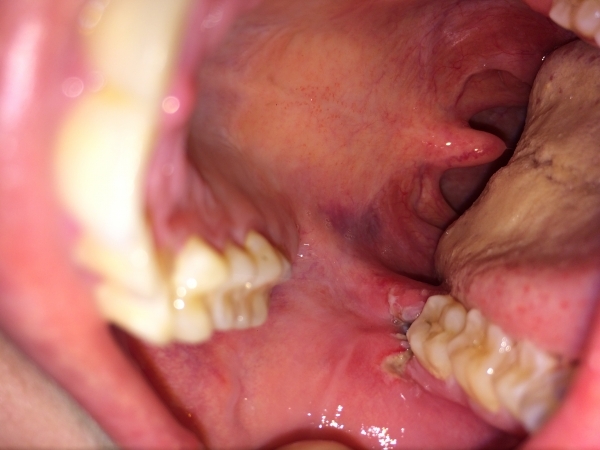

Вчера удалили зуб мудрости на правой стороне внизу, зацепили щеку, сильная боль, было сильно больно глотать, правая сторона горла. Думала, все пройдёт сегодня, но начался гной, глотать все также очень больно. Посмотрела горло, а там на небе синяк образовался.

Что мне делать? Помогите, пожалуйста. Уже щека, чувствую, распухла немного, как будто что-то мешается.